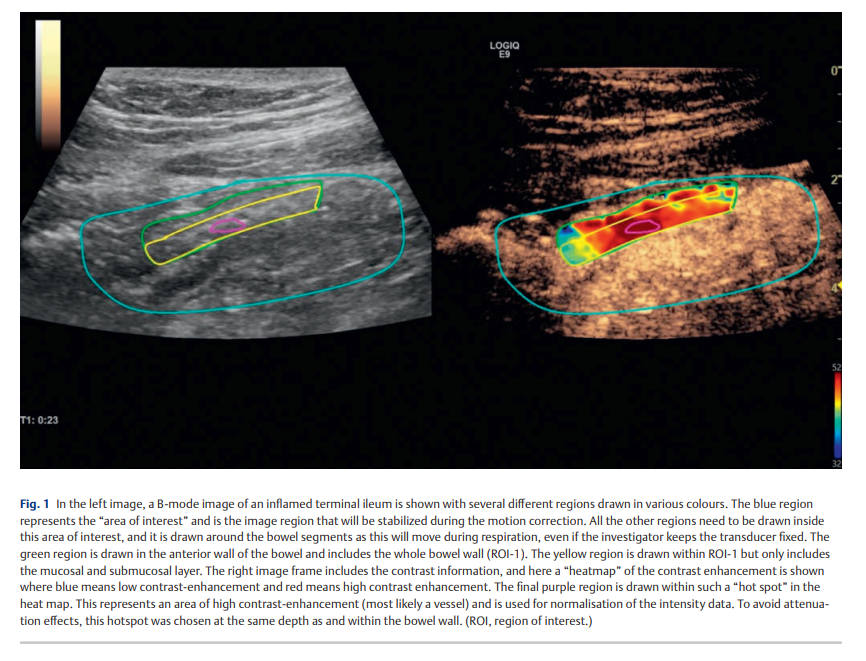

我们前瞻性研究了 2015 年至 2019 年间接受结肠镜检查和 Sonazoid 动态对比增强超声的 48 例克罗恩病患者。我们将最严重病变区域的局部简化克罗恩病内镜评分与 Vuebox 获得的参数进行比较,这些参数包括峰值增强、曲线下流入和流出面积、流入和流出速率以及流入灌注指数。感兴趣区 1(ROI-1)包含肠壁全层,感兴趣区 2(ROI-2)包含黏膜和黏膜下层。使用线性数据和标准化数据。技术失败或拟合优度值 <80% 视为检查失败。

动态对比增强超声检查的可行性为 73%。线性数据中未见显著结果(p>0.05)。在 ROI-1 和 ROI-2 的标准化数据中,局部简化克罗恩病内镜评分与峰值增强(r=0.38 和 r=0.35)、流入速率(r=0.34 和 r=0.34)、流入灌注指数(r=0.40 和 r=0.37)显著相关,并且在 ROI-2 中与曲线下流入面积(r=0.36)显著相关。在中/重度活动期患者中,两个感兴趣区的峰值增强、曲线下流入面积、曲线下流出面积、流入速率和流入灌注指数均显著升高(p<0.05)。ROI-1 与 ROI-2 之间的所有参数均存在显著差异(p<0.05)。